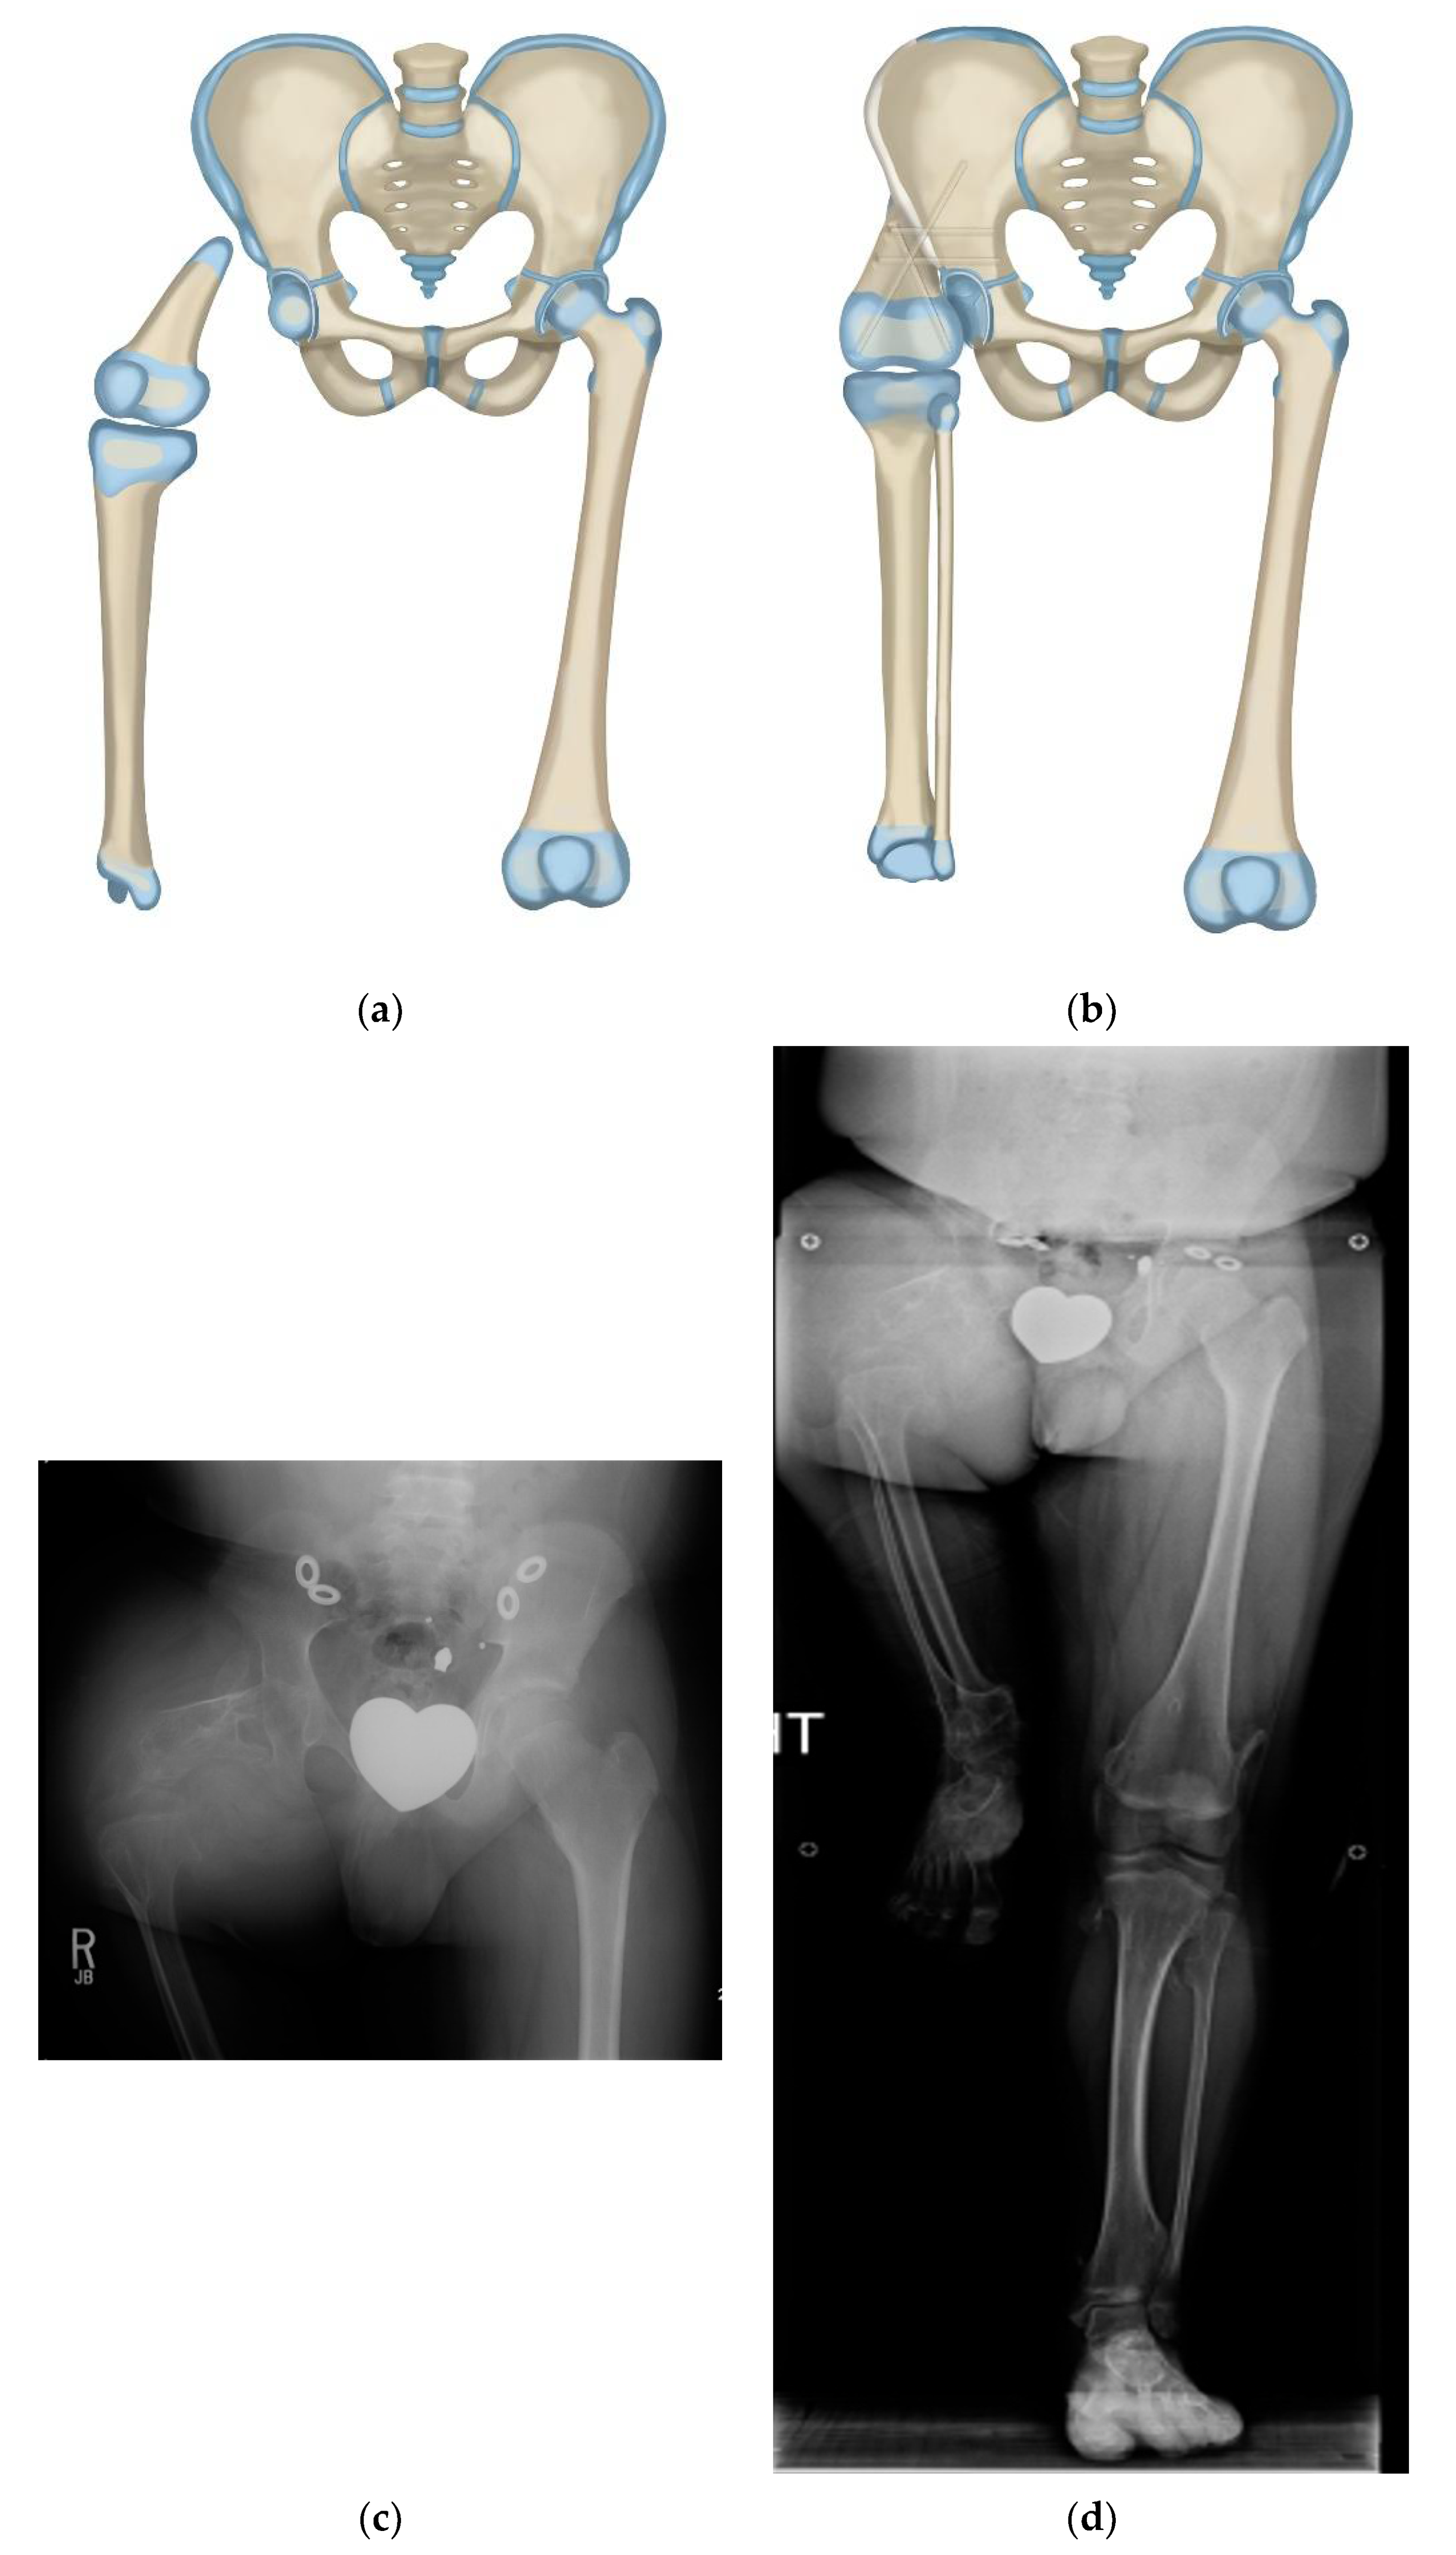

Figure 6.

(a) Illustration of CFD type 1a3 or 1b. (b) Illustration showing the first step which is SUPERhip procedure with resection of knee joint. (c) Illustration showing the second step which is PaleySUPERhip–Van Nes rotationplasty at level of the knee fusion. (d) AP pelvis on 36-year-old man with CFD type 1b with prior failed hip surgery. (e) Standing radiograph in same man showing ankle at level of opposite knee joint. (f) Long lateral and AP radiographs showing the knee joint in the same patient was unstable, deformed and subluxated. (g) Standing radiograph one year after PaleySUPERhip–Van Nes procedure including SUPERhip, knee fusion and supramalleolar osteotomy, wearing rotationplasty prosthetic. Ankle is at level of opposite knee. This procedure greatly improved his quality and of life, gait and function.